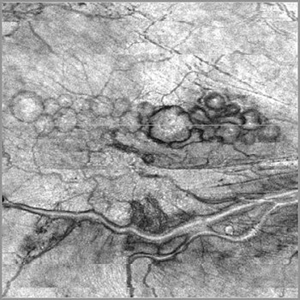

Cavernous Hemangioma of the Retina

A female patient, 13 years of age, with complaint of low vision in her left eye, had esotropia in this eye. In the examination of fundoscopy and color photograph, we observed a pattern of multiple formations venous aneurysm with aspects of bunches of grapes in the nasal cavity above, which is characteristic of the cavernous hemangiomas of the retina.

Photographer: JEFFERSON R SOUSA - Study Center and Ophthalmological Research Dr. Andre M V Gomes, Institute Dr. Suel Abujamra São Paulo-Brazil

Imaging device: Topcon TRC-50VT, Film, Kodak Ektachrome 160 - ASA 100 / 35mm, field of 35 degrees. Flash 100.

Condition/keywords: cavernous hemangioma of the retina, tumor

Cavernous Hemangioma of Papilla

Male patient, 46-years-old, complaining of loss of the nasal field. The funduscopy revealed important vascular changes with aspects of bunch of grapes above-papillae.

Imaging device: Zeiss / VisuCam-500 - Angulation of field photo of 45 Degrees, flash 16, digital magnification 4x

Condition/keywords: cavernous hemangioma of papilla, cavernous hemangioma of the retina, tumor